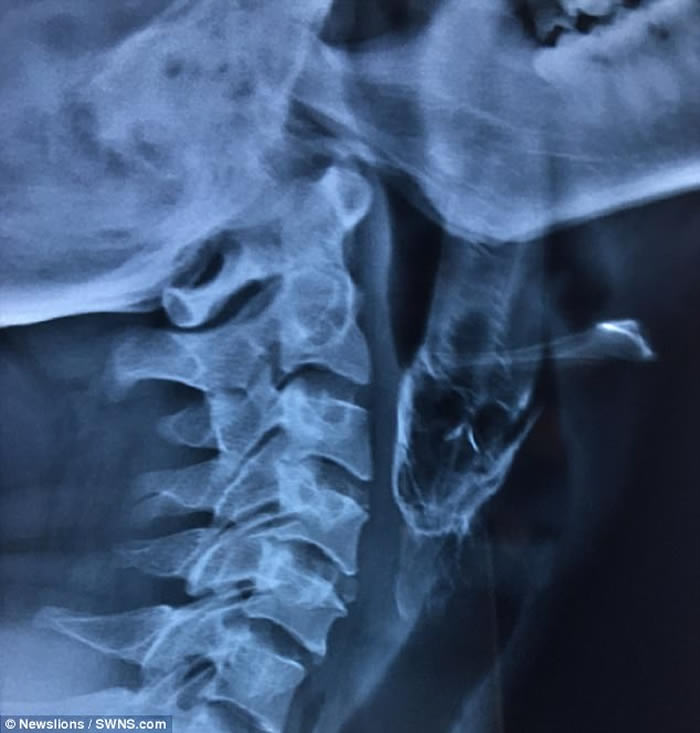

男事主达什(Santosh Dash)当日在池塘徒手捉了一条攀鲈,后者竟飞进他的口中,卡在喉咙,致几乎窒息。达什被送院后,医生设法取出活鱼但不果,需转送距达什村庄200米外的医院。

医生指,达什入院时,可从其口腔中望到鱼尾,随即送入急症室接受局部麻醉,再撑开其口用钳把鱼拉出。医生表示,达什的喉咙遭攀鲈割伤,需以鼻胃管喂食10天,现时已出院。